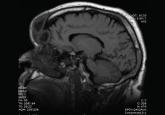

ArticleA 60-year-old man with forehead swellingAuthor:Brandon Miller, MDPublish date: February 1, 2016CT and MRI revealed infection in close proximity to the brain. The patient recovered with antibiotics and surgery.Read More